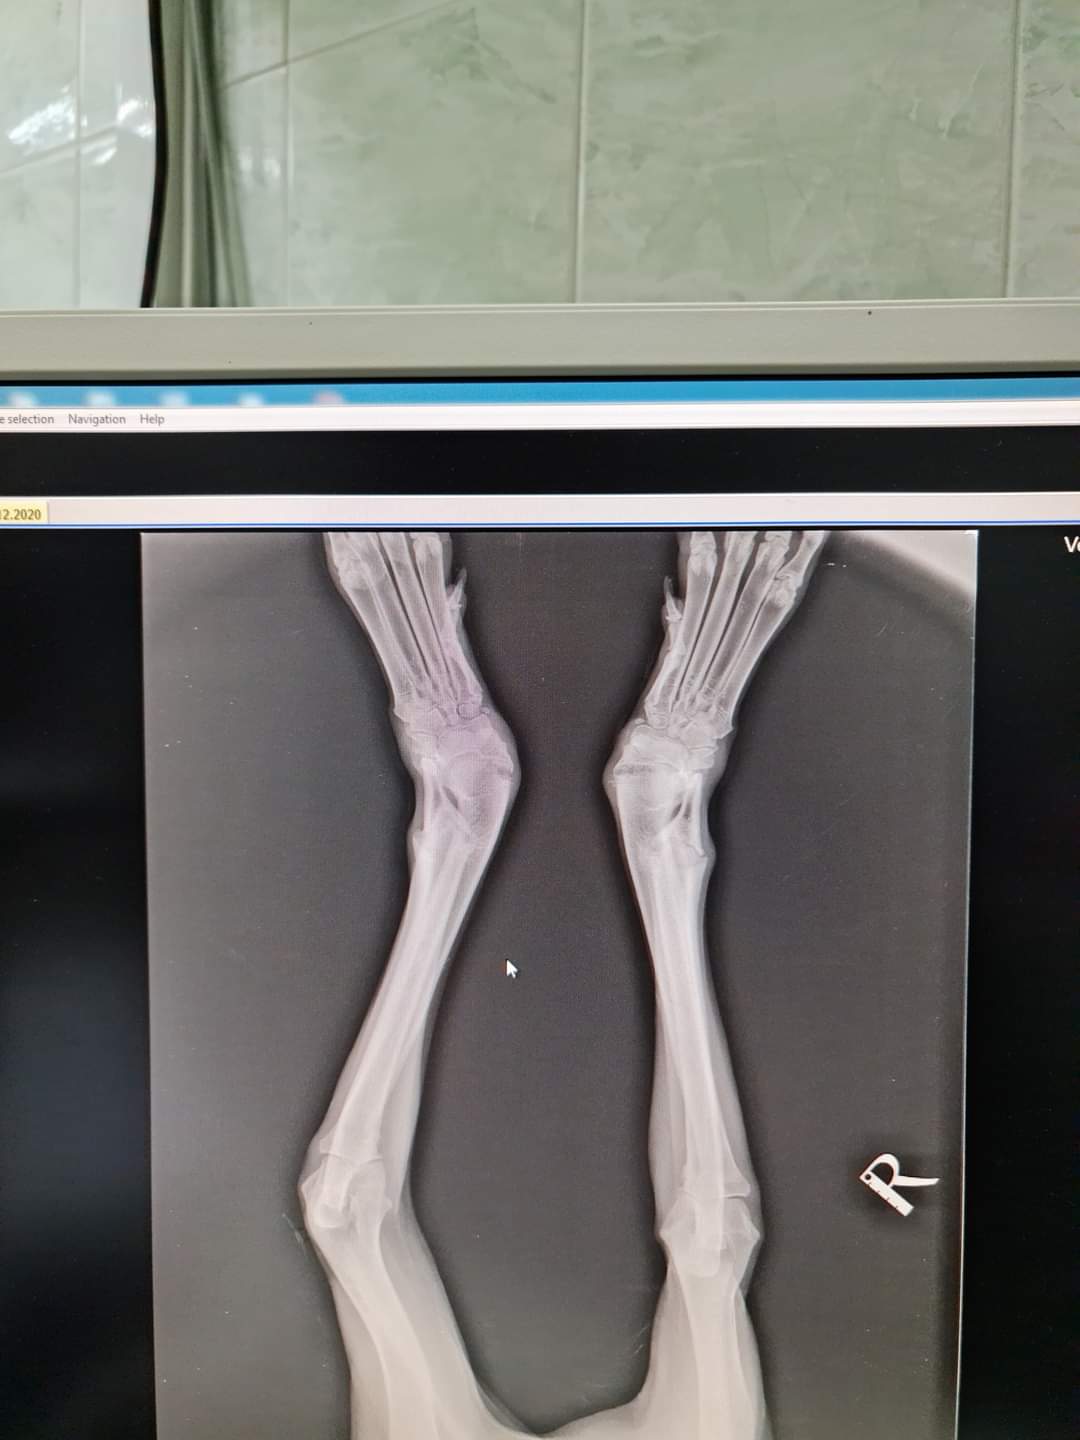

Кучето Кайра е с гени да бъде голямо по размер куче. За съжаление обаче по време на растежа си е получавала твърде малки количества минерали, които да направят костите и здрави и е довело до тяхната деформация. Най засегнати да двете лъчеви и лакътни кости. При нормално израснали кучета, те са прави кост, които се свързват с костите на китковата става и раменната кост. При Кайра костите са се изкривили и получили ъгъл напред, което допълнително променя обременяването на китката и води до изкривяване на крайника навън. Кайра е още много млада, около десет месечна, което означава че разтежните зони още са активни.

За да помогнем на Кайра да използва предните си крака нормално е нужно да се „изправят“ деформираните кости. Това се постига чрез корекции на самите кости и поставяне на метални импланти, които да държат костите изправени и допълни елементи, които да задържат китковата става фиксирана така,че крачето да може да се движи напред, а не в страни.

Това може да се постигне с поредица от операции, отделно за всеки крак

Корективна остеотомия и след това панкарпална артродеза